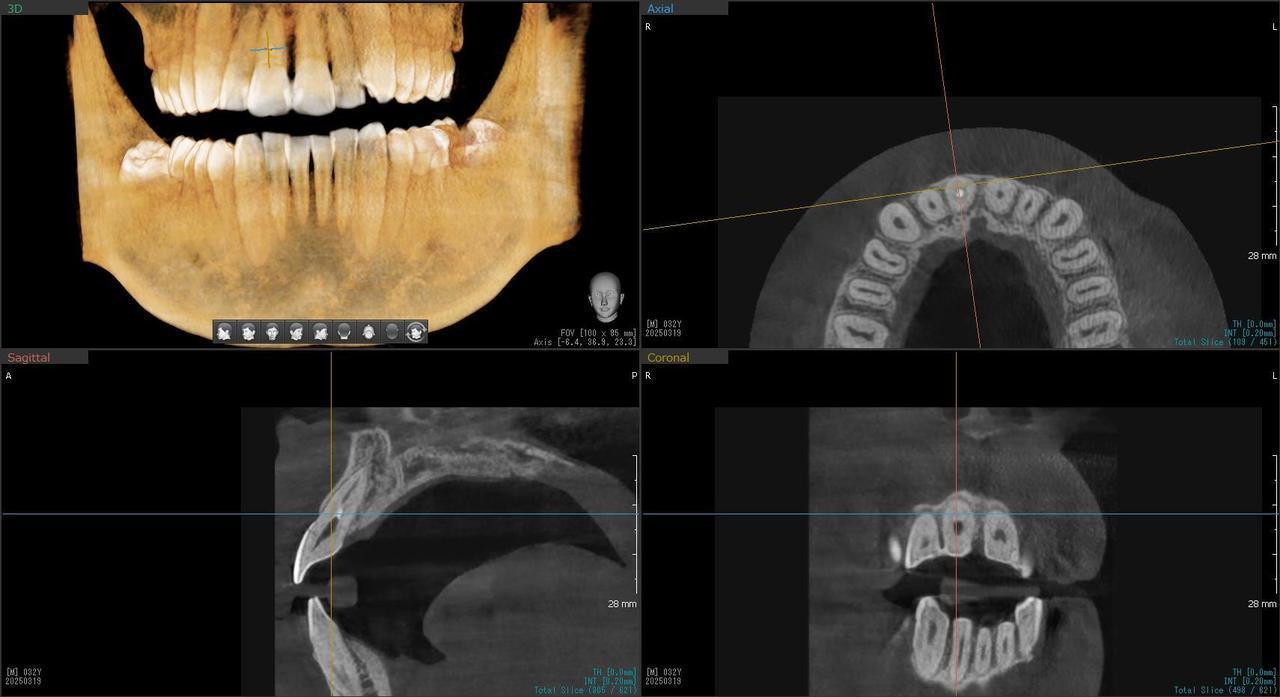

2.右上2番の前歯が、虫歯で折れてしまって、インプラント埋入当日に抜歯とインプラント埋入、仮歯まで装着して、2か月半で最終的な歯を入れたケース

Before

枚方市のインプラントの症例

術後の仮歯をつけた状態

After

K・Y 様 女性 50代

右上の2番3番がカリエスと食いしばりにより、破折したため、インプラント治療を希望

治療法としては、右上2番3番ともに、保存は、難しそうだったっが、患者様の希望もあり、右上3番は、歯を保存して、保険治療の前歯部のCADCAM冠で、どうしても残すことが無理であった右上2に関しては、インプラント手術、当日に抜歯をおこない、インプラント埋入をおこない、仮歯まで装着して、硬いものは、避けてもらうことを条件に食事ができる状態と歯がある状態で手術を終えました。その後、で2か月後にデジタル印象をおこない、2か月半で最終的なジルコニアの歯を入れ、治療を終えることができました。

治療の期間・回数:約2か月半、5回

治療の価格:404000円(税込)

治療費の内訳:インプラント基本料(フィックスチャー(ストローマン BLTインプラント使用)及び手術費用、投薬費用、レントゲン費用、インプラント上部費用(アバットメントおよびジルコニア)クラウンの費用用)360000円(税込み)オプション費用:抜歯即時埋入即時負荷加算(人口コツ費用を含む) 費用 44000円(税込み)

治療のリスクや副作用:手術後に、痛みや腫れ、出血、合併症などを引き起こす可能性があります。噛む感覚がご自身の歯と異なる場合があります。見た目がご自身の歯と異なる場合があります。手術後にメインテナンスを継続しないと、インプラントが抜け落ちる可能性があります。